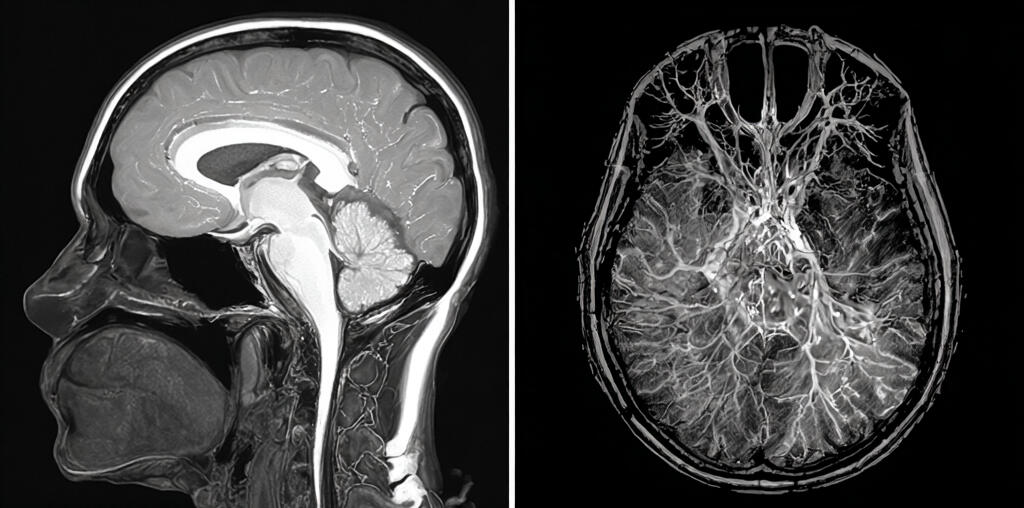

Healthcare is built to react, not anticipate. Routine checkups, lab tests, and one-off scans capture only single moments in time. Even MRI - the most powerful way to see inside the body - is usually used after something goes wrong, and even then we look at just one image. It’s like judging a movie from a single frame. We miss the story.

Delta scanning uses AI to compare high-resolution MRI scans over time, tracking how the body is changing frame by frame. It turns MRI into an active, continuous view of health. It can detect early signs of cancer, spot brain atrophy before memory loss begins, and identify narrowing arteries that could lead to stroke or heart attack - so we can see what wasn’t there before.